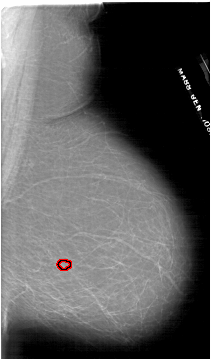

FILE: A_1798_1.RIGHT_MLO.OVERLAY

TOTAL_ABNORMALITIES 1

ABNORMALITY 1

LESION_TYPE MASS SHAPE LOBULATED MARGINS ILL_DEFINED

ASSESSMENT 4

SUBTLETY 4

PATHOLOGY BENIGN

TOTAL_OUTLINES 1

BOUNDARY